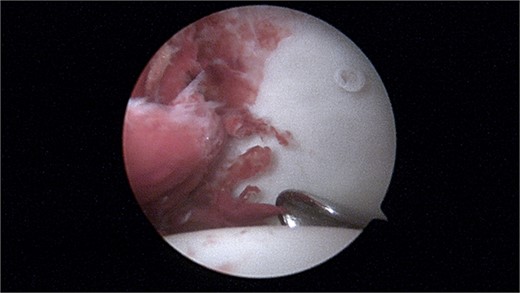

During the arthroscopic procedure, extensive synovial proliferation and a well-defined mass were identified within the joint space. The mass was excised, and the synovium was sampled for histopathological evaluation (Fig. 2). The pathology report confirmed the diagnosis of an SGCT, a rare entity within the hip joint (Fig. 3).

Histopathology showing proliferation of mononuclear synovial cells with oval or polygonal shapes and multinucleated giant cells resembling osteoclasts.

The histopathological examination revealed a nodular proliferation of mononuclear and multinucleated giant cells, consistent with an SGCT. These tumors typically exhibit mild to moderate cellular atypia without significant mitotic activity, which contributes to their localized and aggressive nature. The tumor’s rare occurrence in synovial tissue underscores its complexity and the need for precise diagnostic methods [3].